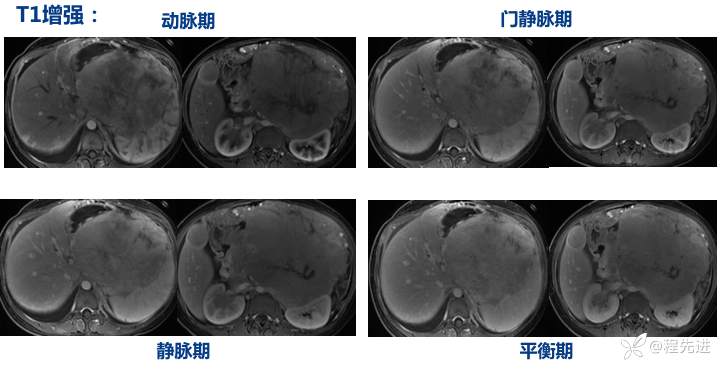

T1、T2: